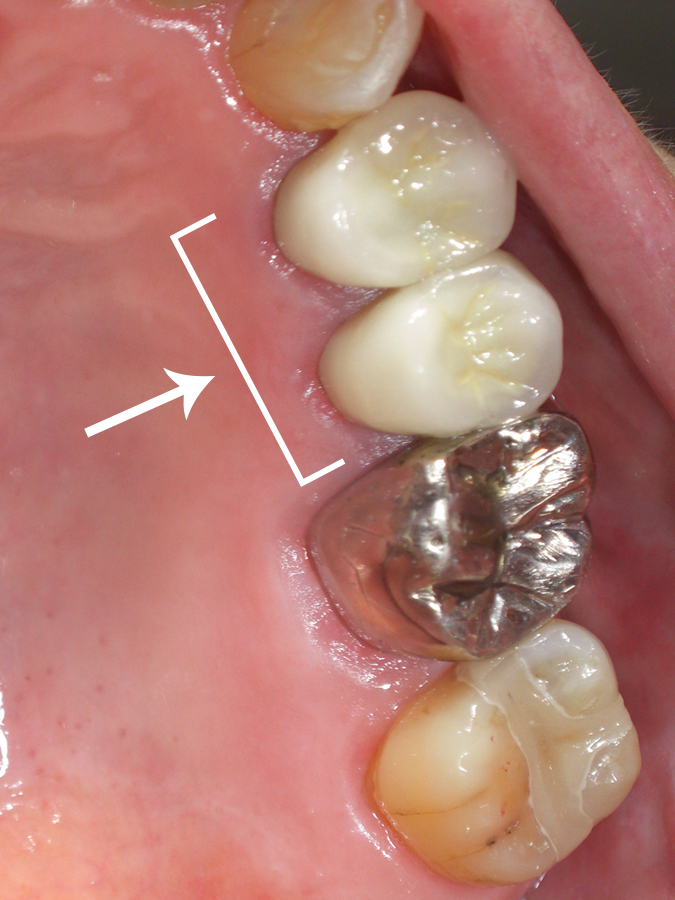

60代女性(左上7番)広陵町在住

〔術前〕

長年悩んでいた銀色のかぶせ歯2本をセラミックに交換し、又今回は奥歯の詰め物もセラミックにして大変気に入って嬉しく思っております。